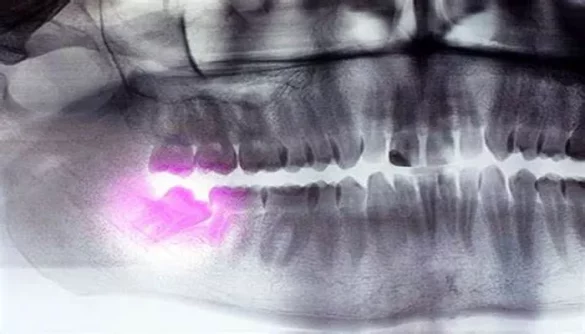

When wisdom teeth are impacted, it means they are unable to fully emerge through the gums due to lack of space, misalignment, or other reasons. The teeth may remain partially or completely trapped beneath the gum line. Impacted wisdom teeth are common and can occur in both the upper and lower jaw.

Partial bony impaction: The tooth is partly covered by bone but may be partially visible.

Complete bony impaction: The tooth is fully trapped within the bone, making it unable to emerge.